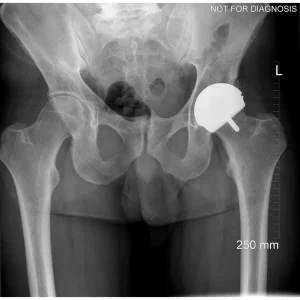

Hip resurfacing is a type of hip surgery used to treat hip arthritis, most commonly in younger and more active patients. Unlike a total hip replacement, hip resurfacing preserves more of your natural thigh bone. Instead of removing the entire femoral head (ball at the top of the thigh bone), the damaged surface is trimmed and covered with a smooth metal cap. The hip’s socket on the pelvis is also fitted with a metal cup.

Dr Grammatopoulos will review your X-rays and other imaging carefully to determine whether hip resurfacing is an appropriate option for you.

Hip Resurfacing

- Preserves more natural bone (the femoral head is capped rather than replaced)

- Uses a larger ball size, which may reduce the risk of dislocation